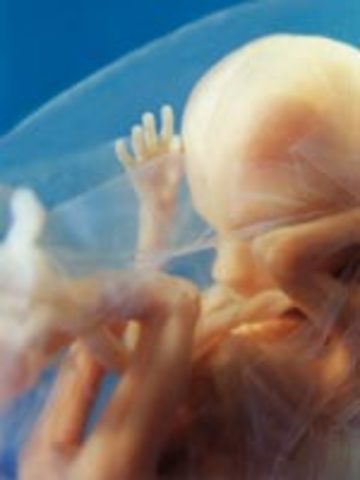

• Week 5: Embryonic Stage Beginning

Week 5: Embryonic Stage Beginning

The Embryo is begging to grow by double it's size it was before. The placent and Amniotic sac is now being formed.

Facts: -A blastocyst is a cluster of 500 cells

-A fibrin clot closes the hole to the uterus cavity